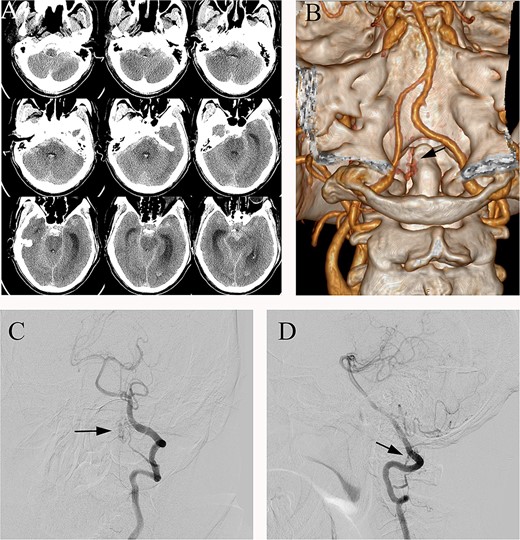

A 70-year-old male presented to the emergency department with sudden dizziness, severe headache, and persistent vomiting lasting 12 hours. He had no past history of major trauma, other diseases, or surgery. Initial head computed tomography (CT) revealed.

SAH predominantly in the posterior fossa, which was around the medulla oblongata, in the prepontine cistern and interpeduncular cistern (Fig. 1A). The following CT angiography (CTA) showed an abnormal vascular structure around the C1, but the image was not clear (Fig. 1B). Further digital subtraction angiography (DSA) revealed an arteriovenous fistula located at the C2 level, supplied by a branch of the left vertebral artery (Fig. 1C and D).

(A) Preoperative head CT, (B) CTA and (C, D) DSA identified the fistula (arrows) in the left lateral dural membrane and confirmed the intradural origin of the drainage vein.